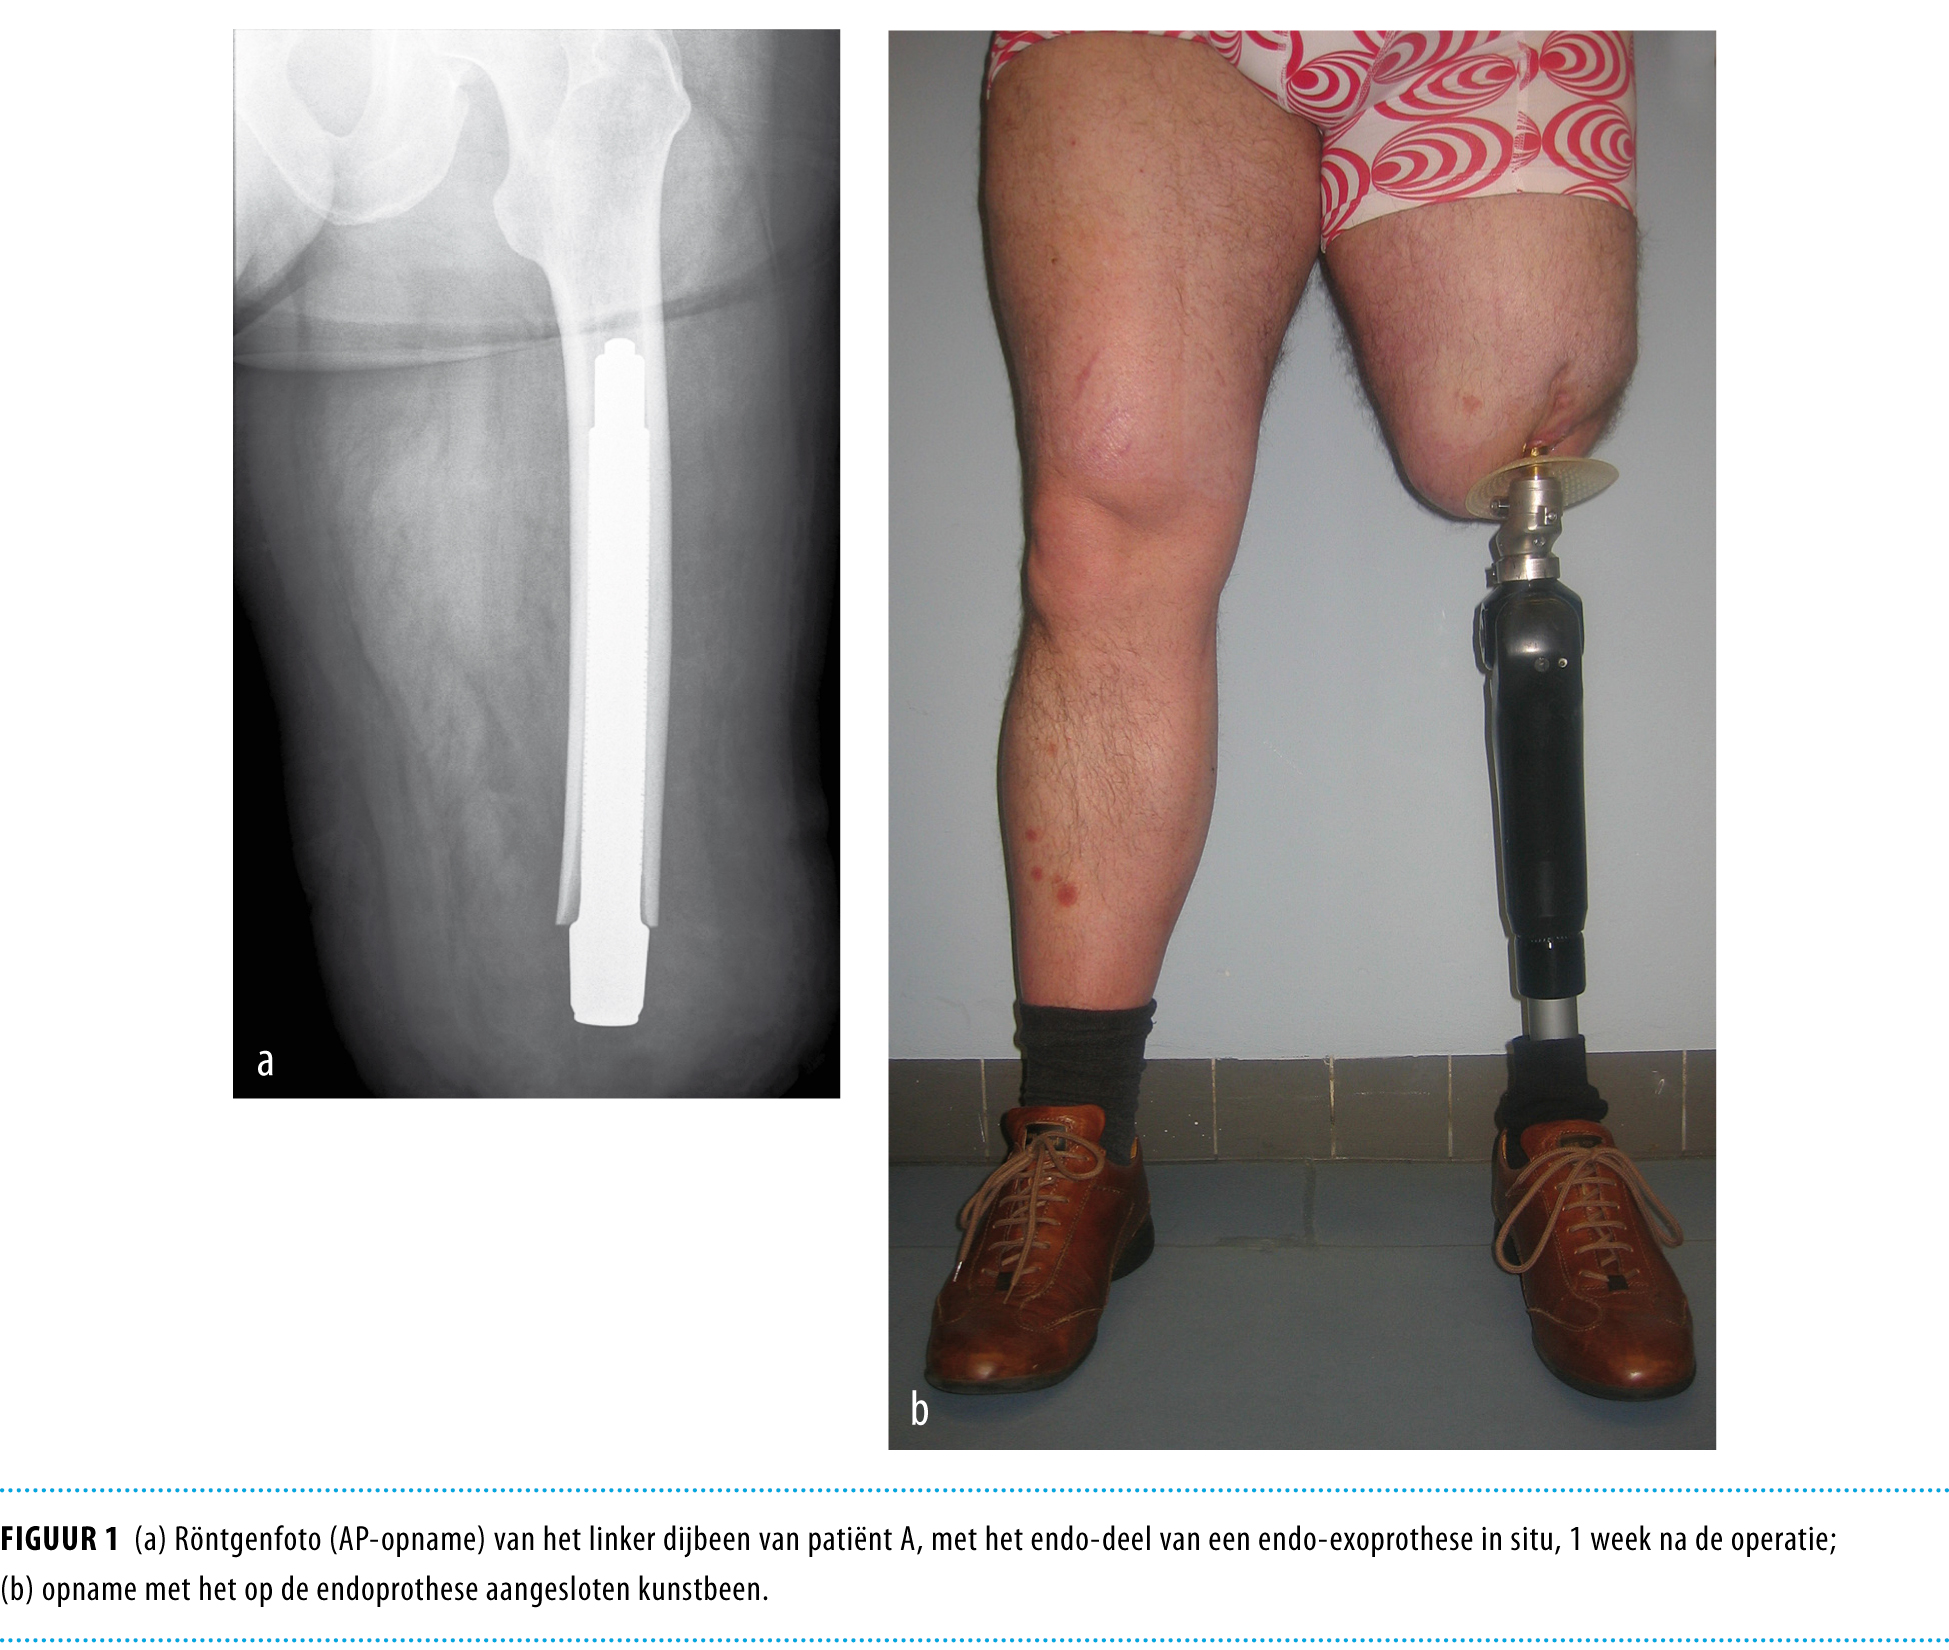

- Klikprothese Endo Exoprothese Voor Patienten Met Een Problematische Amputatiestomp Nederlands Tijdschrift Voor Geneeskunde - Nog Geen Half Jaar Geleden Kreeg Ik Na Een Ongeluk Een Amputatie Aan Mijn Been.